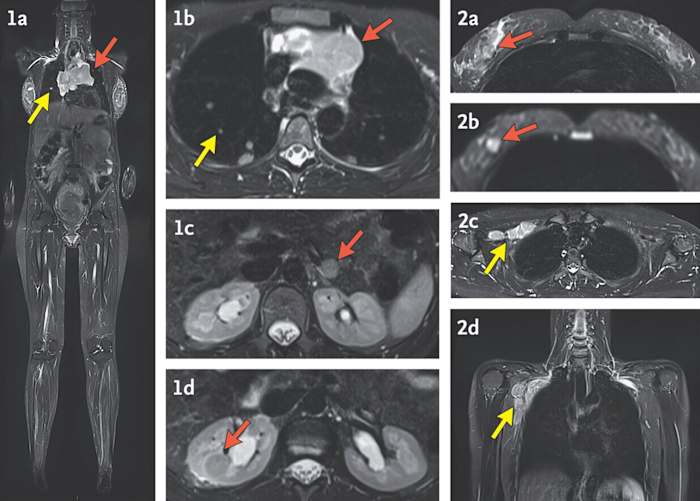

In de studie werd gekeken naar wat er vervolgens moest gebeuren, en de onderzoekers concludeerden dat het het beste is om een ​​MRI van het hele lichaam te doen om kanker op te sporen. Een lichamelijk onderzoek of het afnemen van een familiegeschiedenis is niet voldoende, zei Bianchi.

Ongeveer vijf jaar geleden begonnen commerciële laboratoria die deze tests uitvoeren en artsen vrouwen met ongebruikelijke resultaten over het onderzoek te vertellen. De National Institutes of Health betaalde studievrijwilligers om naar het onderzoeksziekenhuis in Bethesda, Maryland te reizen, waar de deelnemers hun familie- en medische geschiedenis lieten beoordelen, een volledig lichamelijk onderzoek uitvoerden, MRI-scans van het hele lichaam en andere tests uitvoerden.